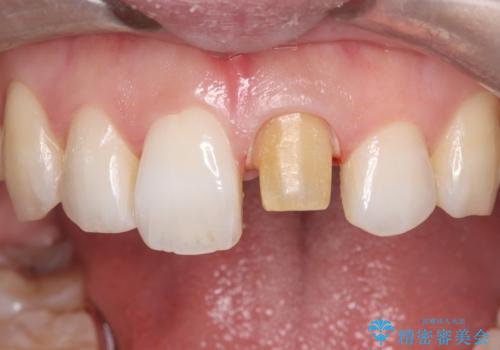

前歯の気になる変色を解消。再根管治療とオールセラミックで自然な美しさへ

- 「以前、他院で神経を取った前歯がだんだん黒ずんできた」という見た目の改善を主訴にご来院されました。 診査の結果、神経を取り除いた後の歯(失活歯)特有の変色が起きており、さらに根の先端にわずかな影が見られたため、内部で感染が起きている可能性がありました。

そこで、まずは土台を外して根の内部をきれいにする再根管治療を行い、基礎をやり直した上で、透明感の高いオールセラミッククラウンで被せ直す治療計画を立案。単に白くするだけでなく、再発を防ぎ、長期的に美しい状態を保つことを目指しました。

精密な再根管治療: 古い充填材を除去し、歯科用顕微鏡を用いて根管内を徹底的に清掃・殺菌しました。根の先まで確実に薬剤を詰め直すことで、将来的な根尖病変(根の先の膿)のリスクを最小限に抑えました。

土台(ファイバーコア)の構築: 金属の土台は将来的な変色の原因となるため、光の透過性が高く、歯のしなりに近い性質を持つファイバーコアを採用。これにより、被せ物の透明感を損なわず、歯の破折も防ぎます。